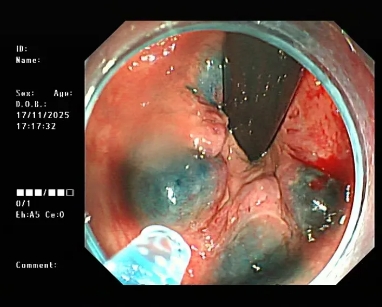

简单说,痔疮硬化治疗就是通过细针将“硬化剂”注射到内痔的黏膜下或痔核内。硬化剂会让痔核周围的组织产生炎症反应,逐渐形成纤维条索,把扩张的血管“扎紧”,同时让痔核萎缩、变小,最终解决便血、脱出等问题。

整个过程不用开刀,创伤特别小,有点像平时打“肌肉针”,多数人不会有明显痛苦。

图片

△内镜下硬化治疗